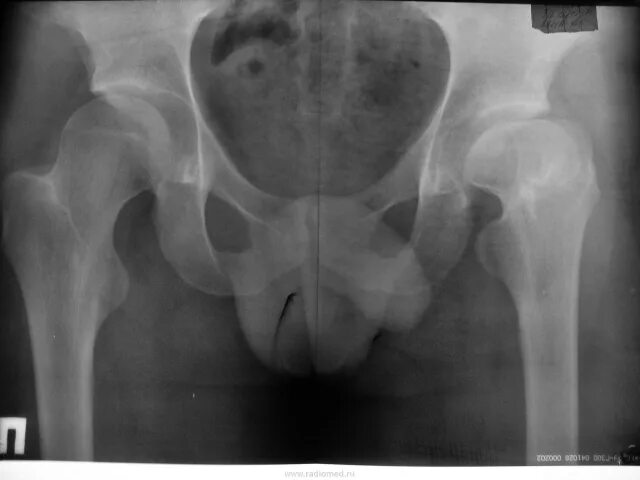

Доа тазобедренных суставов 1 степени что это